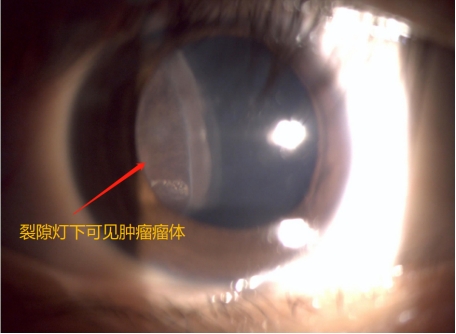

孙大卫在裂隙灯显微镜下发现晓琳的右眼内有一肿瘤,散瞳后肉眼可见瘤体。进一步检查发现,肿瘤位于患者右眼颞侧12点至6点钟位,纵径接近180度,从晶状体蔓延到眼底赤道部,横径超过15mm(而正常人的眼球直径约23mm),肿瘤在眼内脉络膜生长,瘤体向眼球内突出,高度约12mm。综合测量评估后专家认为肿瘤占据眼内体积的一半以上,且肿瘤生长速度较快,已经造成患者视物的遮挡,并逐渐出现肿瘤相关的眼内并发症,渗出性视网膜脱离,继发性白内障等,病情仍有进一步恶化的可能,建议手术治疗。